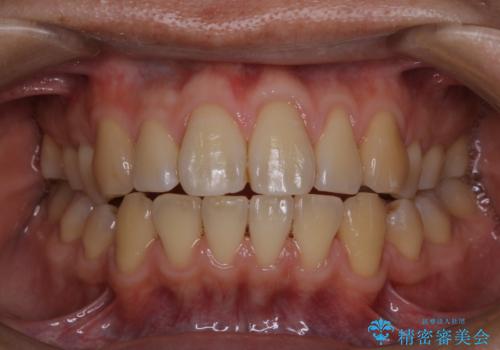

電子タバコによる着色をPMTCできれいに落とす

タバコによるヤニ、着色、歯の汚れをPMTC(60分コース)で除去。